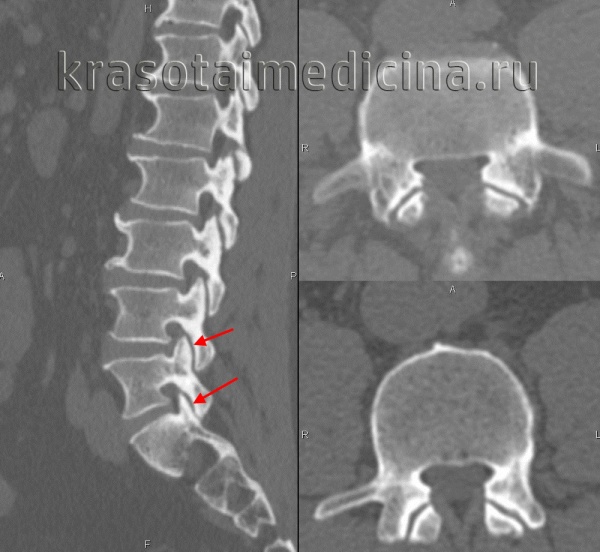

Индексы ASDAS, по-видимому, лучше, чем BASDAI, в связи с более строгой валидностью и высокой дискриминантной способностью. Индексы ASDAS «работают» при АС, ранних формах спондилоартропатий, рентгенонегативном осевом и периферическом АС. С помощью индексов ASAS определяются неактивная болезнь, умеренная, высокая и очень высокая активность заболевания при соответствующих им значениях индексов ASDAS (1,3, 2,1 и 3,5 единицы). Интервал изменения ≥ 1,1 единицы соответствует клинически значимому улучшению, а интервал ≥ 2,0 единиц — значительному улучшению [4]. По мнению экспертов, ASDAS не более 2,1 является целью лечения Т2Т [5]. Нами ниже предложен алгоритм лечения аксиального АС (рис. 1). Однако данные строгих клинических испытаний, способных доказать данную концепцию, пока отсутствуют. Актуальность этих поисков демонстрируют результаты неуклонного прогрессирования болезни, требующего хирургического вмешательства, которые представлены на рисунках 2 и 3.

КТ поясничного отдела позвоночника. Деформирующий спондилоартроз. Умеренно выраженные дегенеративные изменения дугоотростчатых суставов